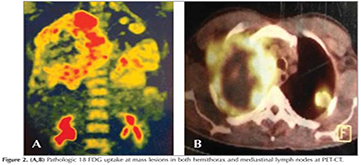

?A 43-year old male patient was admitted with dyspnea and chest pain. On physical examination the breath sounds were markedly diminished at right hemithorax and he had bilateral gynaecomastia. He was a smoker and his smoking history was 22 pack years. A chest radiograph showed opacity involving all zones of right hemithorax and nodular opacities at left hemithorax (Figure 1). A thorax computed tomography (CT) revealed a mass lesion occupying almost all right hemithorax and multiple masses in the left hemithorax. There was also pleural effusion and compression atelectasis at right hemithorax. Laboratory studies revealed a normal complete blood count and serum biochemistry. The erythrocyte sedimentation rate was elevated. Since he was a young patient, had bilateral multiple masses at thorax CT and also had gynaecomastia, a germ cell tumor was suspected and serum β-HCG level was analyzed. The serum β-HCG level was found as elevated: 4261 mIU/mL (normal less then 2.0). Positron emission tomography (PET)-CT revealed pathologic 18 FDG uptake at mass lesions in both hemithorax and mediastinal lymph nodes (Figure 2). Positron emission tomography and ultrasonography showed no gonadal involvement. A bronchoscopy was performed and an endobronchial lesion at the apical segment of right upper lobe was observed. A definitive diagnosis was not achieved by pathologic examination of biopsy specimen, bronchoscopy was repeated and samples were taken by cryobiopsy. Tumor consisted of solid sheets of uniform large tumor cells (Figure 3). Tumor cells were positive with P63 and β-HCG (Figure 4). Keratin 5/6, TTF-1, PLAP and AFP were negative in tumor cells. Mucine carmin staining was negative. We didn't observe syncytiotrophoblast and cytotrophoblast. Our case was β-HCG secreting nonsmall cell lung carcinoma. Since the patient was inoperable, a chemotherapy protocol was started.